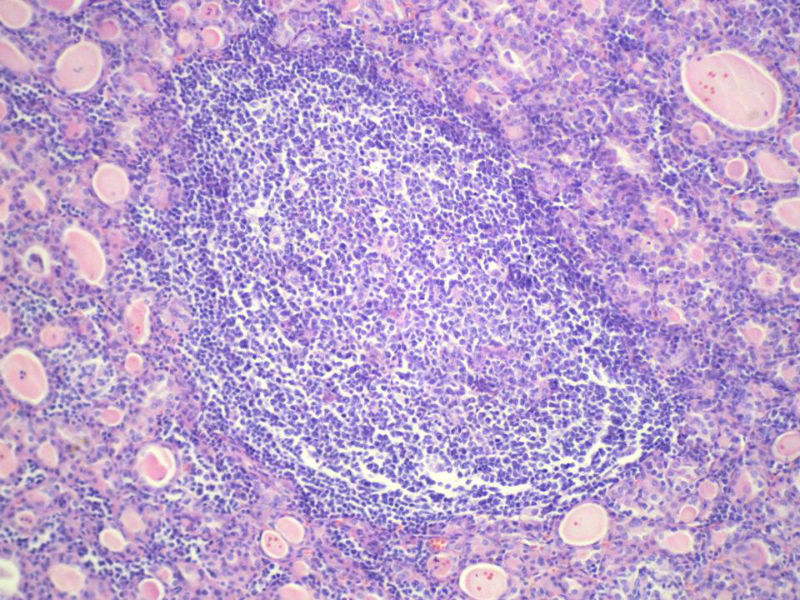

女,60岁,右侧甲状腺肿物两个月,术中见肿块与周围组织无粘连,肉眼,灰红色组织,3X2X2厘米,切面见一直径2.5厘米肿物,包膜完整,灰黄色,质软。

具有桥本氏病的大部分特征,有结节形成,此情况有称之为“结节性桥本甲状腺炎”